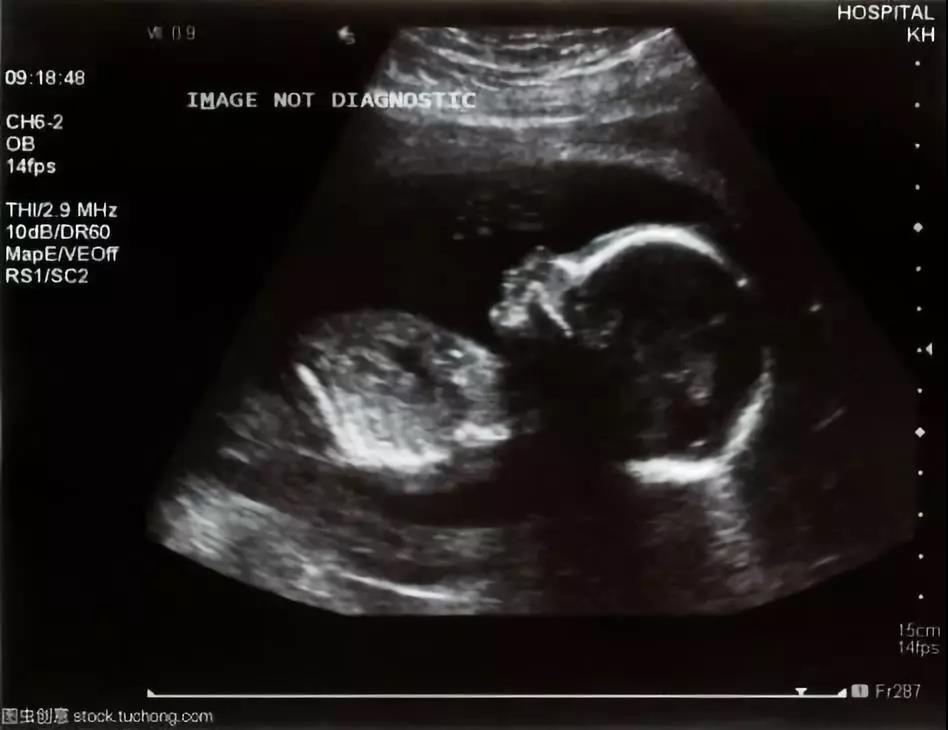

B超是产检中重要的影像学检查手段,在怀孕期间,它可以帮助医生和孕妈了解肚子里宝宝的情况,指导孕期管理和及时发现异常,以确保每个诞生的宝宝都健健康康。作为产检的必查项目,很多孕妈面对B超检查时是一头雾水。二维、三维、四维超声有什么不一样?产检要做几次B超?

医院里最常见的是二维超声,包括黑白B超和彩超,它们的图像是身体里某一切面的平面图。彩超并不是彩色的,全称是彩色多普勒超声,是在黑白B超的基础上增添了血流信息,经过计算机处理不同血流信号会展示出不同颜色。彩超便于判断身体内器官和病变血流情况,利于一些病变的鉴别和诊断。